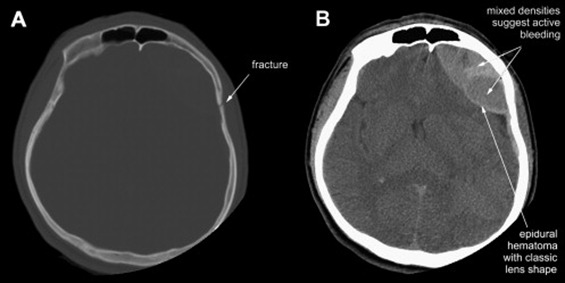

- CT shows biconvex hyperdense collection of blood that DOES NOT cross the suture lines

- CT scan is the radiological investigation of choice

- CT scan will show hyperdense (white) biconvex hematoma that does not cross the sutures